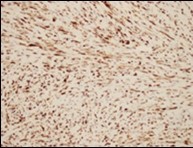

Figure 6.Low grade fibromyxoid sarcoma immune reactive to MUC4(14).

High molecular weight glycoprotein, mucin 4(MUC4) is a sensitive, specific, contemporary immune marker to ascertain and distinguish low grade fibromyxoid sarcoma from histologically identical neoplasms.

A comprehensive (100%), intense, diffuse cytoplasmic immune staining is discerned with MUC4. Gene expression profiling can also be adopted to enunciate MUC4.

Spindle cell neoplasms such as desmoid tumour or soft tissue perineurioma mandating distinction from low grade fibromyxoid sarcoma are immune non reactive to MUC46, 7.